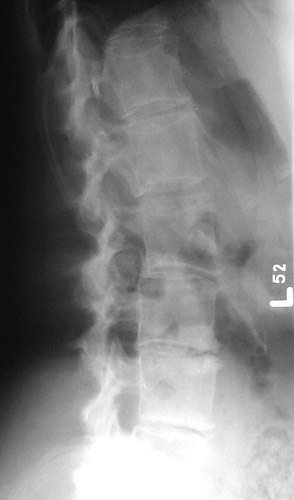

The lucencies seen here in the vertebral column are the result of multiple myeloma. The lucent areas are filled with plasma cells. This patient had back pain.